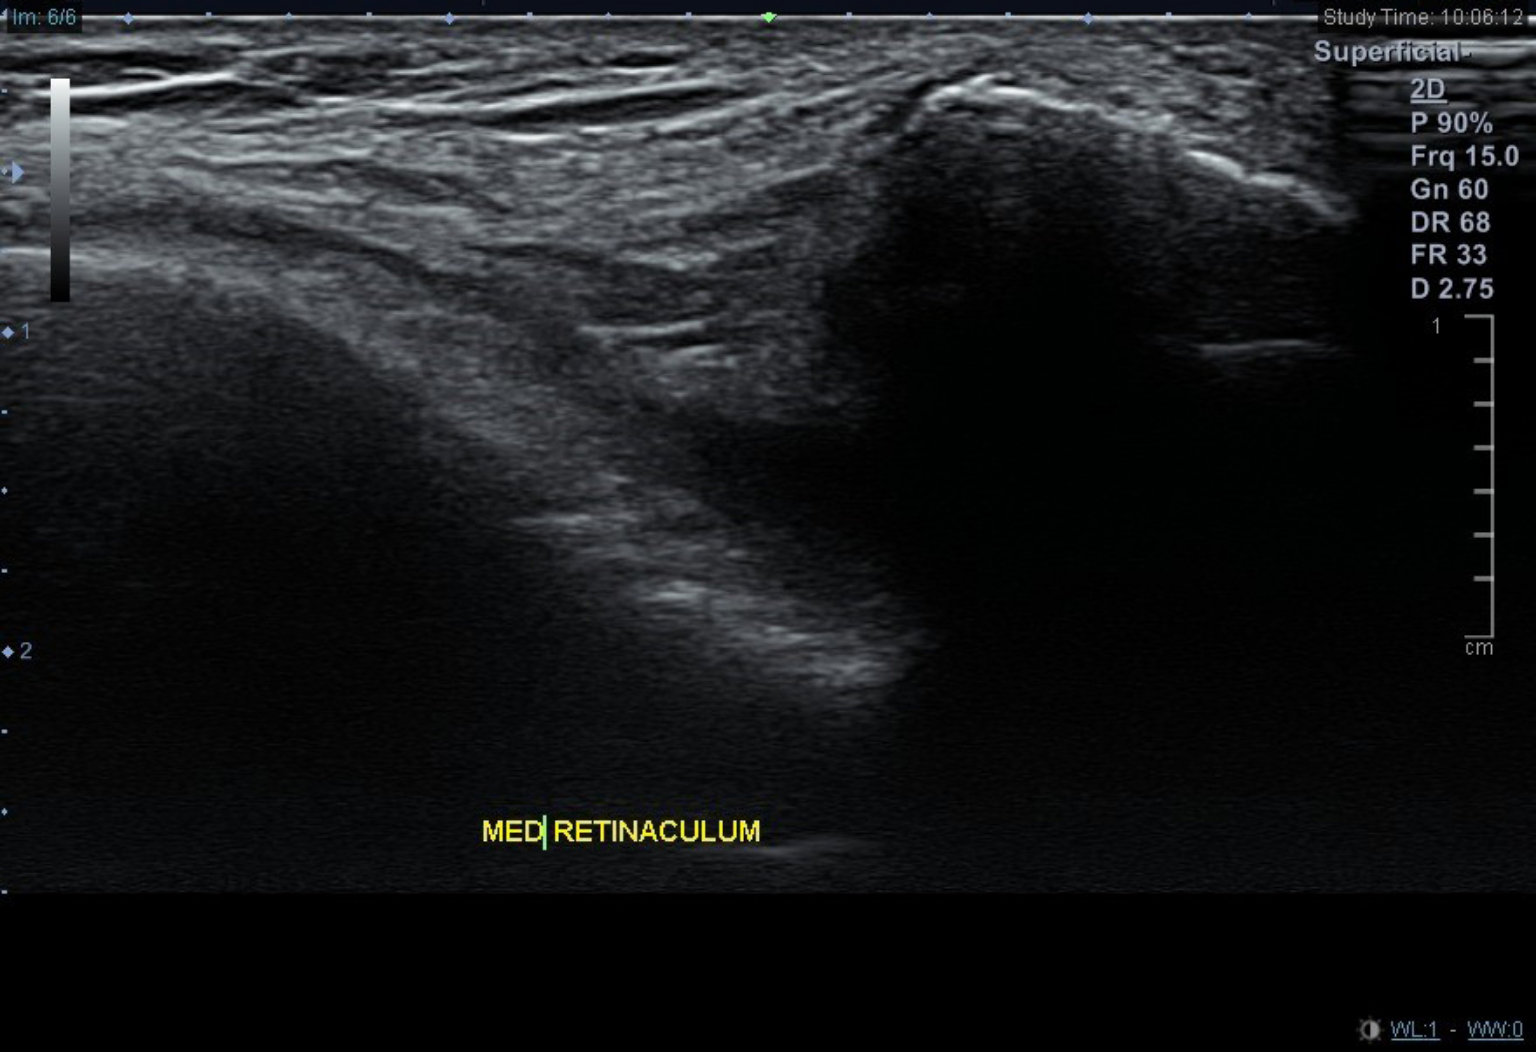

髕骨股骨疼痛症候群的患者常會有跑步時覺得膝蓋內外側的疼痛,或是蹲下站起時膝蓋卡卡或疼痛、膝關節僵硬腫脹、膝蓋彎曲時常有喀啦聲響。針對髕骨股骨疼痛症候群的檢查及診斷,可以藉由病史及理學檢查評估疼痛及受損部位,必要時並配合X光檢查髕骨外翻的程度(圖一)、超音波檢查內外髕支持帶有無受損(圖二)、核磁共振檢查髕骨下的軟骨有無受損情形。